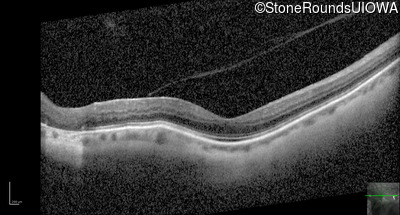

Optical Coherence Tomography - Left - 20/40 +2

Exemplar / OCT Stack

OCT Stack